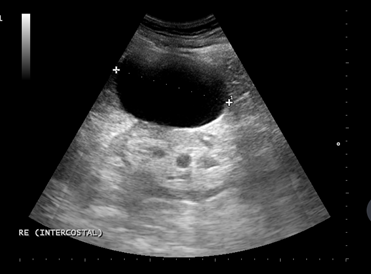

Se realiza ecografía renal a primaria que objectiva una imagen anecoica a nivel de polo superior de riñón izquierdo de 13 x 9 cm que no capta Doppler compatible com un quiste simple renal (Bosniak I).